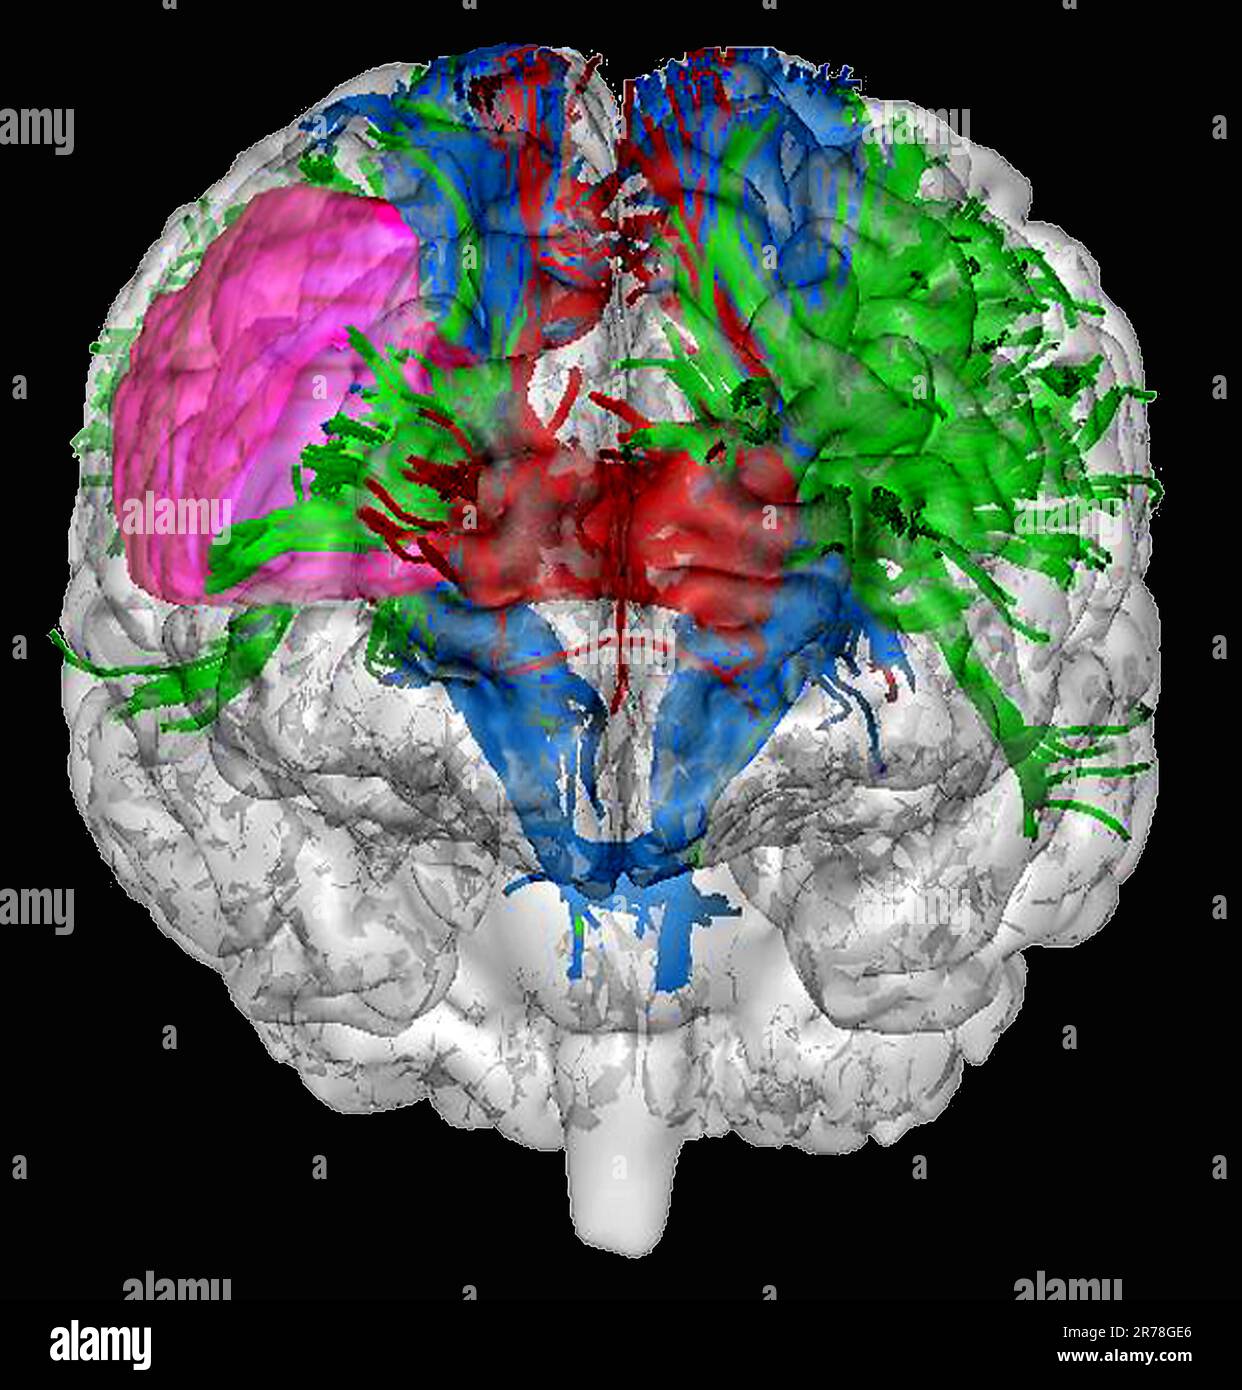

Wenn wir von einer Marklagerläsion sprechen bedeutet das, dass Ihr Hirn an genau dieser bestimmten Stelle stark, leicht oder mittelschwer beschädigt ist Eine Hirnläsion ist eine Art Anomalie im Gehirn , die normalerweise durch eine Krankheit oder Verletzung verursacht wird 1 Was ist eine Läsion? 2 Ursachen 3 Wann zum Arzt? 4 Symptome und Verlauf 5 Diagnose 6 Komplikationen 7 Behandlung und Therapie 8 Aussicht und Prognose 9 Quellen

Präfrontaler Cortex Anatomie und Klinik MediKarriere. Eine Hirnläsion ist eine Art von Anomalie im Gehirn, die normalerweise durch eine Krankheit oder Verletzung verursacht wird 1 Was ist eine Läsion? 2 Ursachen 3 Wann zum Arzt? 4 Symptome und Verlauf 5 Diagnose 6 Komplikationen 7 Behandlung und Therapie 8 Aussicht und Prognose 9 Quellen

SLAP Läsion Was ist das? Was kann man dagegen machen? Operation und Physio. Wie ernst sind Hirnläsionen und wie werden sie behandelt? Hier finden Sie Informationen über diese verwirrend und beunruhigend Gesundheit Die Symptome einer Hirnläsion sind vielfältig und hängen stark von der Lage und Größe der Läsion ab.